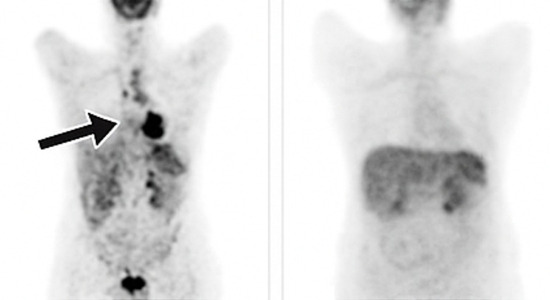

총 3개월간 치료 후 진행된 PET-CT 결과는 의료진도 놀라게 했습니다.

영상상 병변 소실 및 종양표지자 정상화

주치의 평가: 완전관해(CR)